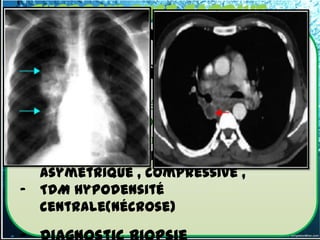

III. Diagnostic

3.2 -2.1. Adénopathies médiastinales

Malignes       topographique

A.2.Lymphome non hodgkinnien

 Les aspects radiologiques ADP

Bilatérales, asymétriques, volumineuses+++,

compressives+/-

 Le diagnostic repose ici encore sur

l'histologie.

 TDM indispensable au bilan de la

dissémination de la maladie, en

particulier à l'étage thoracique,

surtout si les radiographies